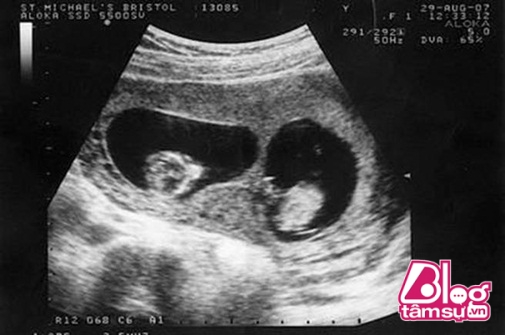

Old  Default Siêu âm thai đôi, cả nhà “hốt hết cả hoảng” khi thai phụ để ra …

Công nghệ phát triển và mọi người đã có thể biết trước giới tính của thai nhi. Nhưng không thể ngờ lại có nhầm lẫn như thế này. Đã sẵn sàng tâm lý đón 2 đứa con sinh đôi chào đời nhưng cô gái thật không ngờ đây là những gì bác sĩ lôi ra từ bụng của mình.

Đây là câu chuyện hết sức kỳ lạ của cô gái trẻ có tên Xiaomei, 25 tuổi, đang sinh sống tại Trung Quốc. Sau nhiều lần đi siêu âm, kiểm tra sức khỏe thai nhi các bác sĩ đã khiến đôi vợ chồng rất hạnh phúc với kết quả sinh đôi.

Trong suốt quá trình mang thai, Xiaomei vẫn thường xuyên siêu âm và kiểm tra sức khỏe thường xuyên. Các bác sĩ luôn nói rằng, em bé trong bụng cô gái vẫn rất khỏe mạnh và phát triển bình thường.

Sau 37 tuần mang thai, Xiaomei thấy đau bụng và gia đình đã đưa cô cấp cứu tại bệnh viện. Các bác sĩ cho rằng, cô đã đến ngày sinh và họ ngay lập tức làm các thủ tục để cô và em bé trong bụng chào đời.

Sau ca phẫu thuật, các bác sĩ vô cùng bàng hoàng sau khi chứng kiến những đứa bé được sinh ra từ bụng của Xiaomei. Mặc dù đã được siêu âm sinh đôi nhưng sau ca phẫu thuật những bác sĩ đã mổ được 3 đứa bé chào đời.

Ca phẫu thuật khiến cô gái cùng gia đình hết sức bàng hoàng, bất ngờ vì số lượng em bé trong bụng không giống như kết quả siêu âm của các bác sĩ. Đây được xem là niềm vui bất ngờ đối với Xiaomei cùng người chồng của mình. Họ không ngờ có thể đón 1 lúc 3 đứa con chào đời. Tuy nhiên, bên cạnh niềm vui thì cũng có rất nhiều nỗi lo về việc nuôi dạy các con nên người.